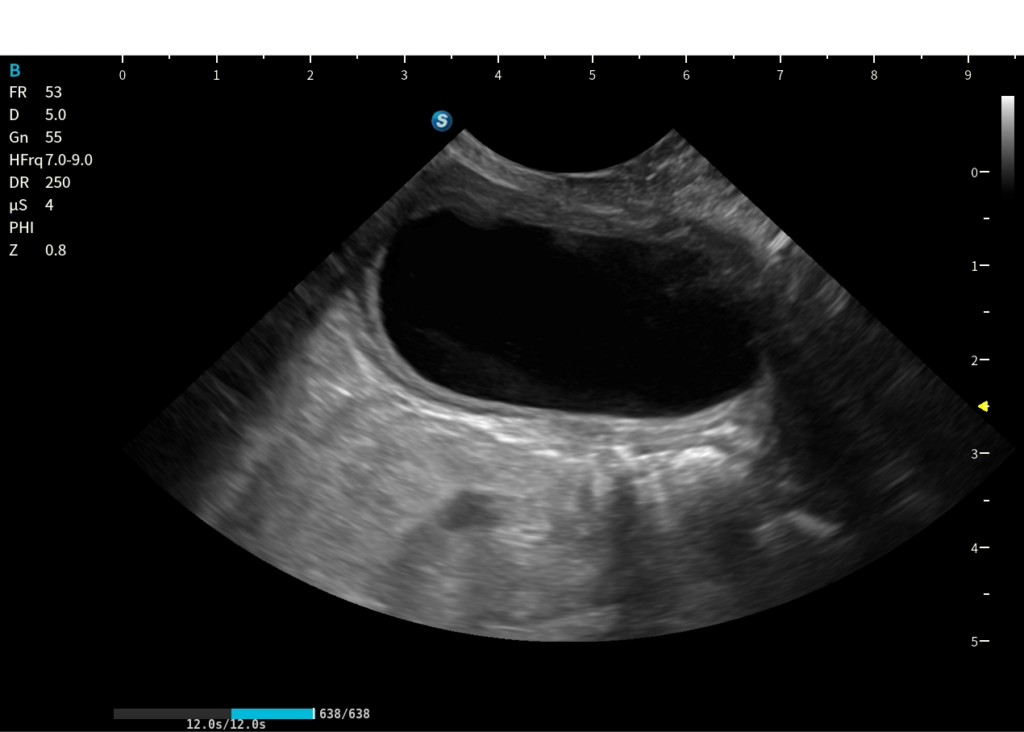

Routine e funzioni avanzate

20260227 095005 ABD 12